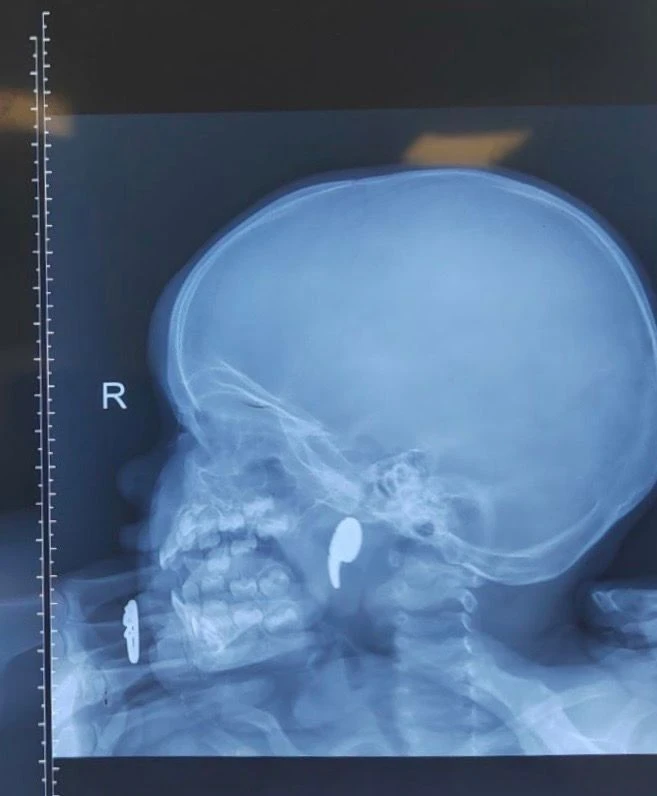

Рентген подтвердил наличие инородного тела. Дежурный ЛОР-врач Марина Перепечена под общей анестезией с эндоскопическим контролем успешно удалила магнит. Через сутки ребёнка выписали домой.